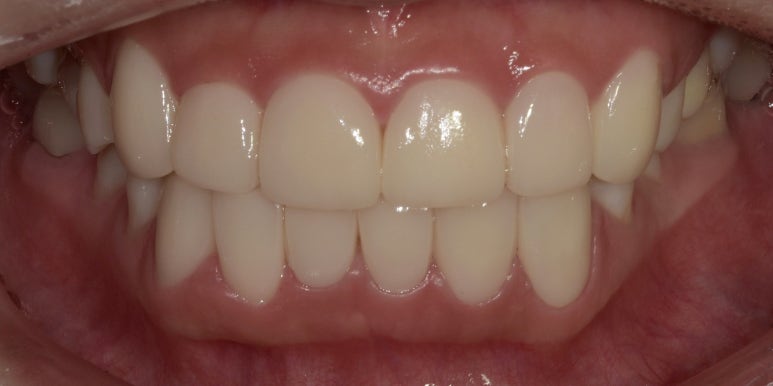

12전치 라미네이트, 크라운 치료 후

2023-07-05

1주일 후 최종적으로 보철물 제작이 완료되어 부착까지 진행해드렸는데요.

바뀐 모습 어떠신가요? 정말 몰라볼 정도로 확연하게 개선이 되었죠?

특히 오른쪽 아래 #42 치아는 기울어져 있던 치아가 반듯하게 개선되어 훨씬 고르게 변했고,

주변 치아와 조화가 잘 이루어지는 모습입니다.

치료가 모두 끝나고 거울을 보여드리니 환자분께서

“이제 마음 편하게 환히 웃을 수 있을 것 같아서 너무 좋네요..

라미네이트 고민 많이 했는데 진작 할 걸 그랬어요”